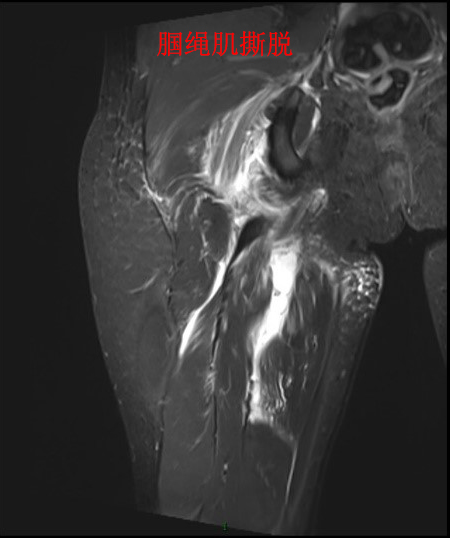

腘绳肌坐骨止点撕脱常见于短跑运动员,多发于跑步中尤其是突然用力起跑,也可发生于篮球运动起跳时。损伤后的表现是臀部疼痛,屈膝、伸髋时疼痛加重,检查可见臀部有瘀斑。我院郑州院区运动医学科黄遂柱博士团队根据小青的情况制定了科学的治疗方案。由于腘绳肌撕脱后发生肌肉回缩,肌肉断端距离坐骨结节止点大于2厘米,如果采取保守治疗则只能靠瘢痕愈合,修复慢而且术后肌肉力量会明显受影响。传统手术方案是切开手术修复撕脱的腘绳肌,但是创伤大,臀部瘢痕会给年轻爱美的女性带来不好的心理影响。为此,黄遂柱博士团队决定采取关节镜微创的手术方案,手术精准、创伤小,又不会留下令人烦恼的皮肤切口瘢痕。术中在关节镜监视下,腘绳肌被准确牢靠地修复到坐骨结节解剖位置,术后患者感到十分满意,表示没有疼痛不适。